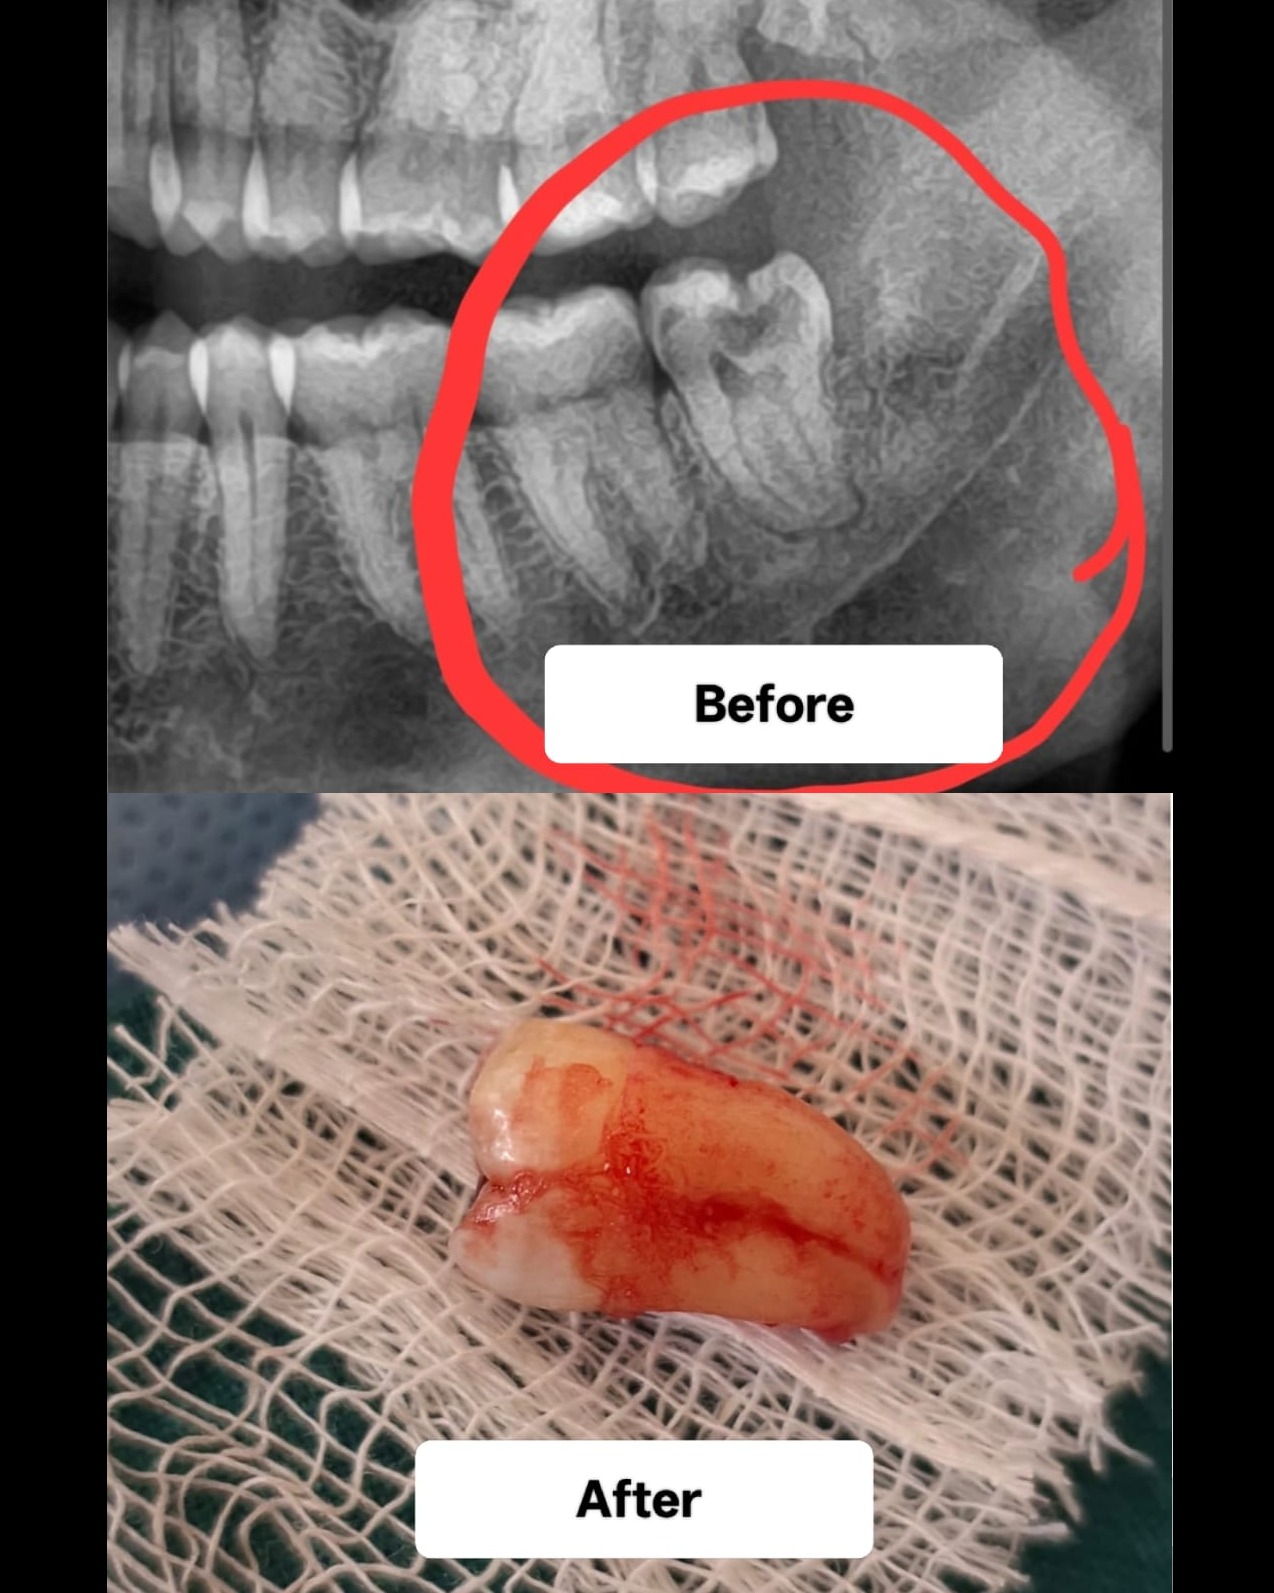

Painless wisdom tooth extraction is achieved using modern local anesthesia, advanced imaging, and specialized surgical techniques to remove impacted or problematic teeth with minimal discomfort. When is Extraction Necessary? Impacted Wisdom Teeth: When teeth are trapped in the jawbone. Infections: Caused by partial eruption or decay. Crowding: Creating pressure and damaging neighboring teeth. Cysts: Developing due to trapped teeth.